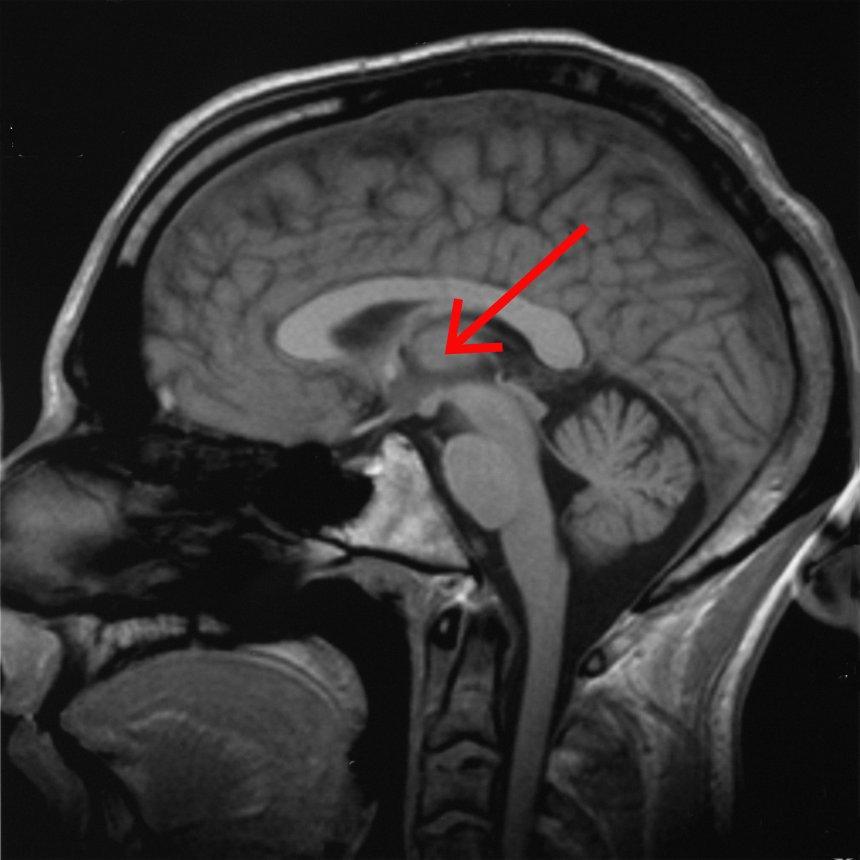

А вот кофеин разворачивает направление

И вот где всё становится реально интересным. При таком же ограничении сна, но с ежедневным кофеином, направление изменений оказалось противоположным в ключевых зонах: в правом таламусе, дорсомедиальной и дорсолатеральной префронтальной коре сигнал серого вещества снижался, тогда как у «декофеиновой» группы он рос.

Это не «чуть меньше выросло». Это другой знак.

И тут появляется неприятная мысль. Кофеин действительно помогает чувствовать бодрость, улучшает внимание и субъективную работоспособность, но на уровне тканевых процессов он может вмешиваться в то, как мозг адаптируется к хроническому недосыпу. Как будто мозг собирался включить компенсаторную перестройку, а кофеин подрезал этот путь и заставил систему работать в другой конфигурации.

Таламус ведёт себя как отдельная планета

Таламус в их выводах выглядит почти упрямым. Он и реагирует заметно, и восстанавливается не так быстро, и связь с A1-рецепторами у него не такая прямолинейная, как у других кластеров. Авторы прямо обсуждают, что таламическая пластичность может идти через иные механизмы и что будущие работы должны внимательнее посмотреть на A2A-рецепторы.

Если отвлечься на секунду, это логично интуитивно. Таламус — один из ключевых узлов регуляции бодрствования и сна. И когда ты пять дней подряд «режешь» сон, а сверху накрываешь кофеином, странно было бы ожидать, что он отреагирует так же, как кора.